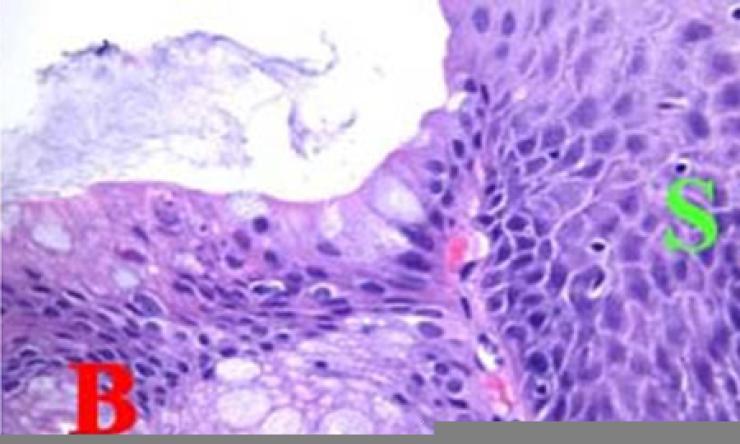

“Under the microscope, Barrett’s lesions show increased cell proliferation and a disorganized tissue with stomach-like and intestine-like cells where only esophageal cells should be,” Jin said. “If this loss of identity persists in the esophagus, the stage is likely set for cancer development.”

The team also developed a mouse model in which Sox2 could be selectively turned off in the esophagus. These mice showed increased cell growth, reduced cell maturation and the appearance of abnormal structures at the junction between the esophagus and stomach – closely mimicking the early stages of Barrett’s esophagus in humans. Without Sox2, the esophageal lining becomes more vulnerable to damage and transformation.